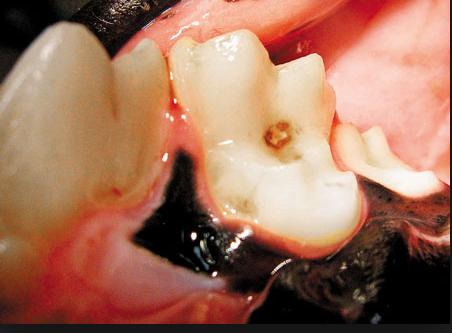

- 牙釉质、牙本质的褪色,即牙齿变色,尤其是前磨牙和磨牙咬合面上的凹陷和裂缝间,牙龈线附近的黄色或棕色沉积物。

- 小狗牙齿上出现的任何一个黑点都有可能是蛀牙的症状。

小狗牙齿发现蛀牙情况